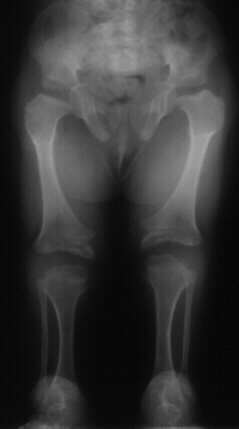

Progressive dislocation of the hip, patella, radial head are often observed.

Hip dislocation and hip dysplasia have been reported, respectively

in 22% and 70% of patients. Delayed femoral head appearing, coxa valga

or, on the contrary, coxa vara are common findings.

Valgus deformity of the knees, associated to flexion contracture,

is another common finding.

- Long bones: they are broad and short. Metaphyses are flared and expanded.

A chevron-like shape is often present in femoral and tibial metaphyses.

Epiphyseal centers appear late and are severely irregular and flat. Ulna

and fibula are usually short.